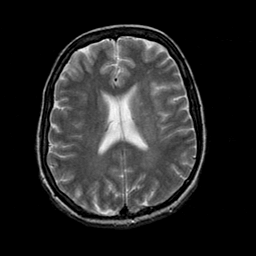

In this paper, we propose a bidirectional learning model, known as dual contrast cycleGAN (DC-cycleGAN), for medical image synthesis from unpaired data. Specifically, a dual contrast (DC) loss is formulated that leverages the advantage of samples from the source domain as negative samples to indirectly build constraints between real source and synthetic images via discriminators, and synthesize images more related to the target domain by enforcing the synthetic images to fall far away from the source domain. In addition, structural similarity index (SSIM) [35] and cross-entropy (CE) [48] are integrated into the DC-cycleGAN structure to avoid disappearing gradient information that is caused by a mean absolute error (MAE) and synthesizing irrelevant images. SSIM considers luminance [35] and CE converges fast as its back-propagation error is less than MSE [28]. As can be seen in Figs. 1 and 2, using SSIM and CE with dual contrast can generate more clear and accurate MR images as compared with that of MAE and MSE, and SSIM and CE without dual contrast loss. Although both SSIM and CE with dual contrast and without dual contrast generate similar CT images, SSIM and CE with dual contrast quantitatively generate better images as shown in Table 4. The experimental results indicate that DC-cycleGAN is able to consider more complex features such as structure in synthesizing images and produce remarkable results as compared with other state-of-the-art methods reported in the literature.

Tables 3 and 4 show the results of MR and CT synthesis, respectively. As can be seen, all components play vital role in both tables. SSIM & CE (w) performs significantly better than other losses in synthesizing MR images. This also can be seen visually in Fig. 1. In contrast, SSIM&CE (w) performs slightly better than SSIM&CE (wo) in synthesizing CT images, both generate more or less similar CT images (see Table 4).